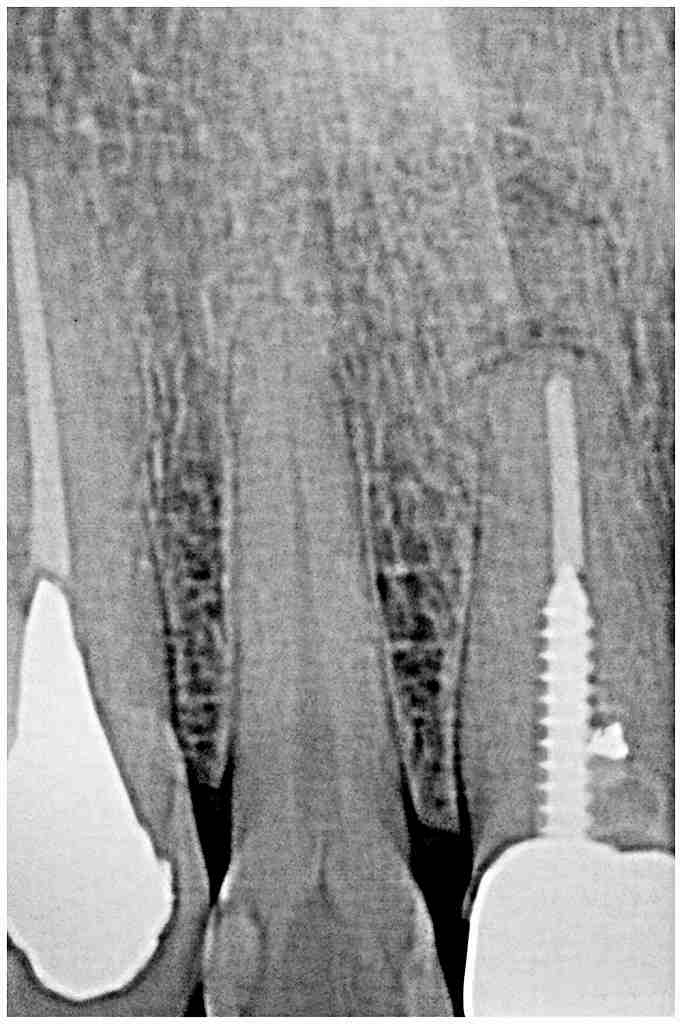

ブログ一覧|広島市安佐南区の歯科医院 ブログ一覧 トップ ブログ一覧 お知らせ スタッフブログ ブログ一覧 2018/04/24 口腔内にて合せたところです。 しっかりした補綴を作っていきます。 2018/04/24 メタルボンドにて作成。 2018/04/24 インプラントブリッジ 2018/04/24 口腔内にてシェード合せを行っています。 この操作が仕上がりの明暗を分けます。 2018/04/24 ジルコニアクラウンの作成 シンタリングからステインまで 2018/04/24 インプラント周囲炎 2018/04/24 歯牙の牽引 2018/04/23 歯牙破折。 牽引にて保存治療へ。 << 1 2 3 4 5 … 660 661 662 663 664 … 870 871 872 873 874 >> Web診療予約 初めての方へ 選ばれ続ける理由 院内設備について 歯が痛いしみる一般歯科 歯がぐらぐらする歯周病 健康な歯を保ちたい予防歯科 子供の虫歯予防をしたい小児歯科 銀歯をセラミックに審美歯科 白い歯を目指しませんか?ホワイトニング 矯正専門医がいるので安心矯正歯科 抜けた歯を補いたいインプラント・入れ歯 医院案内 スタッフ紹介 メリィハウス歯科クリニックオフィシャルホームページ ラベンダー歯科クリニックオフィシャルホームページ お知らせ・ブログ ホーム 診療科目 一般歯科 歯周病治療 予防治療 小児歯科 審美治療 ホワイトニング 矯正歯科 入れ歯・インプラント マウスピース矯正 初めての方へ 院長・スタッフ 設備紹介 医院案内・アクセス メニューを閉じる